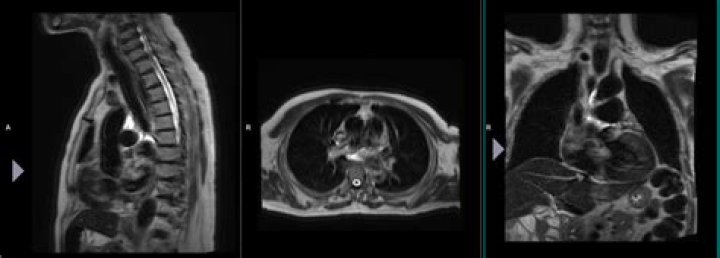

Localizer scans. A set of three-plane, low-resolution, large field-of view localizers are first obtained, equivalent to “scout views” in CT. These localizer images will be used for plotting slices in step 6. 5.

This coordinate system consists of three planes to describe the standard anatomical position of a human. The basic orientation terms for a MRI of the body taken: From the side would be a sagittal plane; from the front, would be a coronal plane; and from the top down, would be a transverse plane.